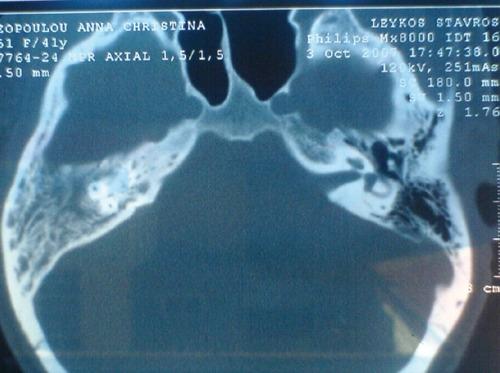

在首次被描述近30年后,艾滋病毒仍然是一种全球大流行病。本文旨在综述目前关于艾滋病毒感染的耳鼻喉(ENT)表现的知识,并介绍现有的诊断和治疗选择。在Medline和其他可用的数据库来源中进行了文献综述。数据分析中还纳入了相关书籍中的信息。众所周知,高达80%的艾滋病毒感染患者最终会出现耳鼻喉表现;其中,口腔疾病似乎最为常见。口咽表现包括念珠菌病、牙周和牙龈疾病、单纯疱疹病毒和人乳头瘤病毒感染、口腔毛状白斑、卡波西肉瘤和非霍奇金淋巴瘤。颈部的耳鼻喉表现可表现为颈部淋巴结病或腮腺肿大。相应的鼻部表现包括鼻窦炎(通常由非典型细菌引起)和过敏性鼻炎。最后,耳部表现包括中耳炎(外耳炎或中耳炎)、内耳受累(感音神经性听力损失、平衡失调)和面神经麻痹(与普通人群相比频率高达100倍)。虽然耳鼻喉症状不能诊断该疾病,但它们可能提示艾滋病毒感染,或与其进展及相应的治疗失败有关。耳鼻喉科医生应了解与艾滋病毒疾病相关的耳鼻喉表现以及相应的诊断和治疗方法。可能需要采取多学科方法为艾滋病毒患者提供适当水平的护理。